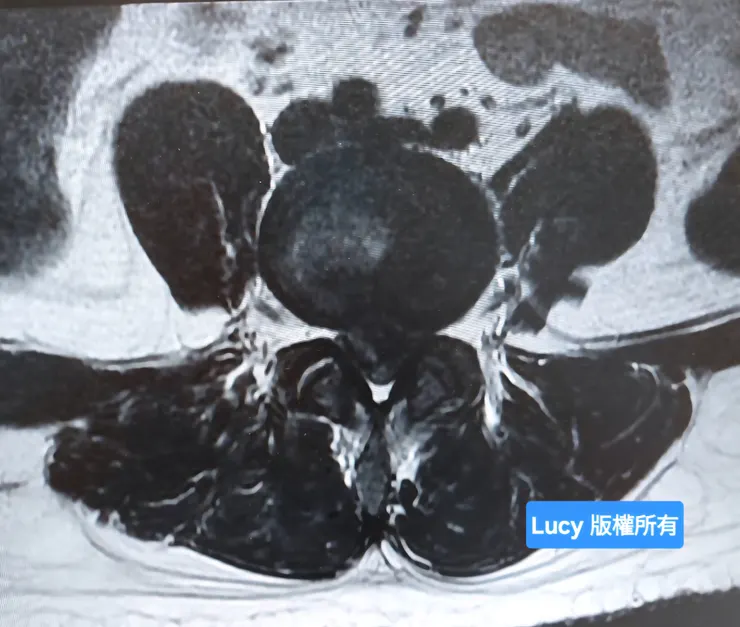

同時,媽媽也在和急診醫生反覆確認病情的嚴重性。感謝這位急診醫師,他依然耐心且親切地向媽媽和電話遠端的阿姨詳細說明:「我的椎間盤不只是突出,而是已經破裂,骨髓核嚴重壓迫到神經,真的必須馬上開刀。」。

核磁共振影像看到第4、5節椎間盤嚴重破裂

核磁共振影像看到第4、5節椎間盤嚴重破裂,已看不到白色脊髓